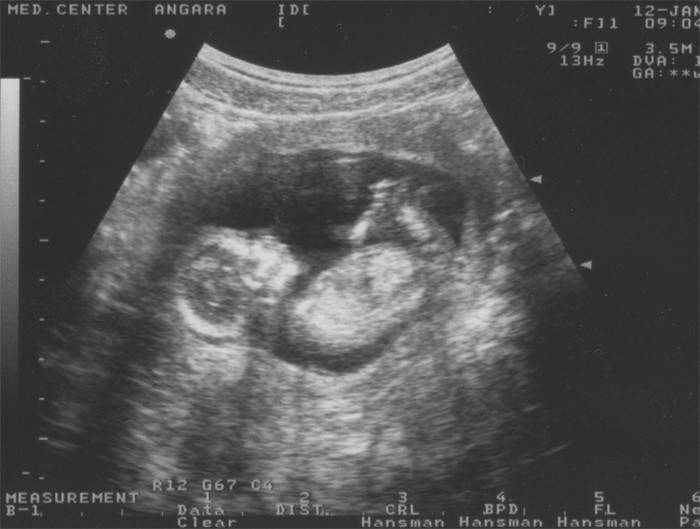

Ultrazvukové vyšetrenie

V 14. týždni tehotenstva môže lekár predpísať prvý plánovaný ultrazvuk, ak tehotenstvo pokračovalo bez komplikácií a neexistovali žiadne náznaky na vykonanie štúdie skôr. V tomto období môže ultrazvuk ukázať pomerne veľké množstvo informácií. Najprv sa vyhodnotí stav maternice a placenty, práca ciev pupočníka a určia sa hlavné ukazovatele ultrazvuku u dieťaťa. Odhadované podmienky a súlad ukazovateľov s podmienkami, ako aj vývoj dieťaťa - sú stanovené jeho hlavné orgány a systémy. V tomto období už môžete dieťa celkom dobre a podrobne rozoznať.

Lekár vyhodnotí hlavné kľúčové ukazovatele ultrazvuku plodu:

- KTR plodu, jeho rast od hlavy po chvostovú kosť,

- biparietal size - veľkosť hlavy plodu,

- obvod hlavy

- obvod prsníka.

- stav nosovej kosti

- fetálna femur

- veľkosť golierového priestoru.

Okrem toho lekár podrobne preskúma štruktúru všetkých orgánov a systémov plodu, vývoj končatín, činnosť srdca a frekvenciu kontrakcií, vyhodnotí štruktúru mozgu, obličiek a močového mechúra. V tomto období môžete často určiť pohlavie plodu, ako aj pomocou ultrazvukového vyšetrenia, aby ste svoje dieťa vyšetrili na vlastné oči.